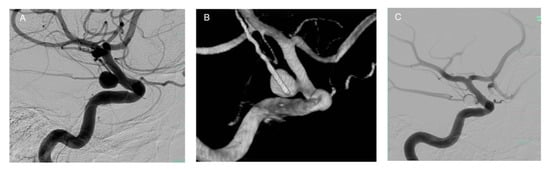

3.6. Intrasaccular Flow Disruptors and Woven Endoluminal Bridge (WEB)

- Dmytriw, A.A.; Salem, M.M.; Yang, V.X.D.; Krings, T.; Pereira, V.M.; Moore, J.M.; Thomas, A.J. Endosaccular Flow Disruption: A New Frontier in Endovascular Aneurysm Management. Neurosurgery 2019, 86, 170–181. [Google Scholar] [CrossRef]

- van Rooij, S.; Sprengers, M.; Peluso, J.; Daams, J.; Verbaan, D.; van Rooij, W.; Majoie, C. A Systematic Review and Meta-Analysis of Woven EndoBridge Single Layer for Treatment of Intracranial Aneurysms. Interv. Neuroradiol. 2020, 159101992090442. [Google Scholar] [CrossRef] [PubMed]

- Haffaf, I.; Clarençon, F.; Shotar, E.; Rolla-Bigliani, C.; Vande Perre, S.; Mathon, B.; Drir, M.; Sourour, N.A. Medina Embolization Device for the Treatment of Intracranial Aneurysms: 18 Months’ Angiographic Results. J. Neurointerventional Surg. 2019, 11, 516–522. [Google Scholar] [CrossRef] [PubMed]

- Perez, M.A.; Bhogal, P.; Moreno, R.M.; Bäzner, H.; Ganslandt, O.; Henkes, H. The Medina Embolic Device: Early Clinical Experience from a Single Center. J. Neurointerventional Surg. 2017, 9, 77–87. [Google Scholar] [CrossRef]

- Sourour, N.-A.; Vande Perre, S.; Maria, F.D.; Papagiannaki, C.; Gabrieli, J.; Pistocchi, S.; Bartolini, B.; Degos, V.; Carpentier, A.; Chiras, J.; et al. Medina® Embolization Device for the Treatment of Intracranial Aneurysms: Safety and Angiographic Effectiveness at 6 Months. Neurosurgery 2017, 82, 155–162. [Google Scholar] [CrossRef]